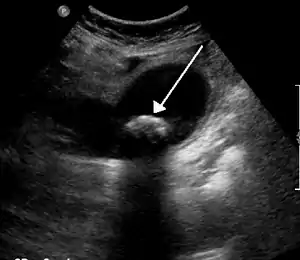

A 1.9 cm gallstone impacted in the neck of the gallbladder and leading to cholecystitis as seen on ultrasound. There is 4 mm gall bladder wall thickening.

Biliary sludge and gallstones. There is borderline thickening of the gallbladder wall.